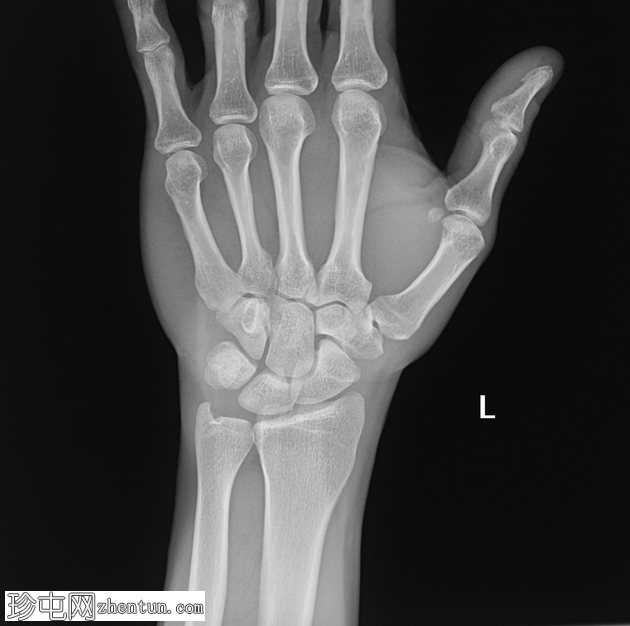

X线片

正位片

左腕关节正位和侧位X线片显示三角骨撕脱性骨折,仅在侧位片上可见,放大锐化后骨折线显示更清晰。